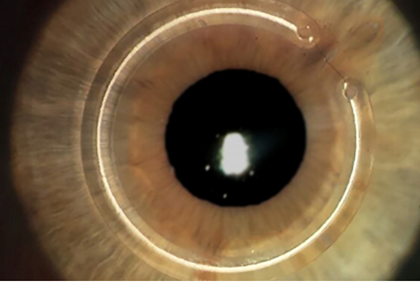

- Implante de anel intraestromal: é uma boa alternativa cirúrgica para se evitar o transplante. Segmentos de anel são implantados no estroma da córnea de maneira muito segura com auxílio do laser de femtosegundo. O objetivo é remodelar a curvatura corneana corrigindo parte da distorçã É indicado em pacientes intolerantes à lente de contato e/ou com irregularidades acentuadas na superfície corneana.